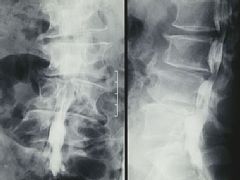

堆骨の後ろ側を上から 下に走る束が神経。 上の方2ケ所が圧迫で 細り、黒く見える。 (左側面) |

| 左側面 | 正面 |